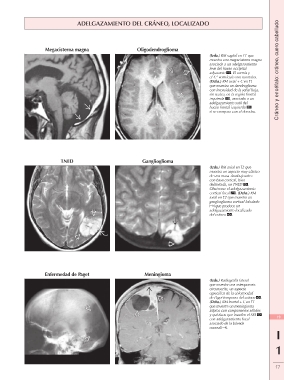

ADELGAZAMIENTO DEL CRÁNEO, LOCALIZADO Cráneo y encéfalo: cráneo, cuero cabelludo

Megacisterna magna Oligodendroglioma

(Izda.) RM sagital en T1 que

muestra una megacisterna magna

asociada a un adelgazamiento

leve del hueso occipital

adyacente . El vermis y

el 4.º ventrículo son normales.

(Dcha.) RM axial + C en T1

que muestra un dendroglioma

con intensidad de la señal baja,

sin realce, en la región frontal

izquierda , asociado a un

adelgazamiento sutil del

hueso frontal izquierdo

si se compara con el derecho.

TNED Ganglioglioma

(Izda.) RM axial en T2 que

muestra un aspecto muy clásico

de una masa «burbujeante»

con base cortical, bien

delimitada, un TNED .

Obsérvese el adelgazamiento

cortical focal . (Dcha.) RM

axial en T2 que muestra un

ganglioglioma cortical lobulado

que produce un

adelgazamiento localizado

del cráneo .

Enfermedad de Paget Meningioma

(Izda.) Radiografía lateral 19

que muestra una osteoporosis

circunscrita, un aspecto I

específico de la enfermedad 1

de Paget temprana del cráneo .

(Dcha.) RM frontal + C en T1 17

que muestra un meningioma

atípico con componentes sólidos

y quísticos que invaden el SSS

con adelgazamiento focal

asociado de la bóveda

craneal .